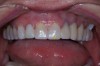

Figure 30  Final restorations.

Figure 30

Figure 31  Technical precision and artistic skill blend into a pleasing smile and a happy patient.

Figure 31